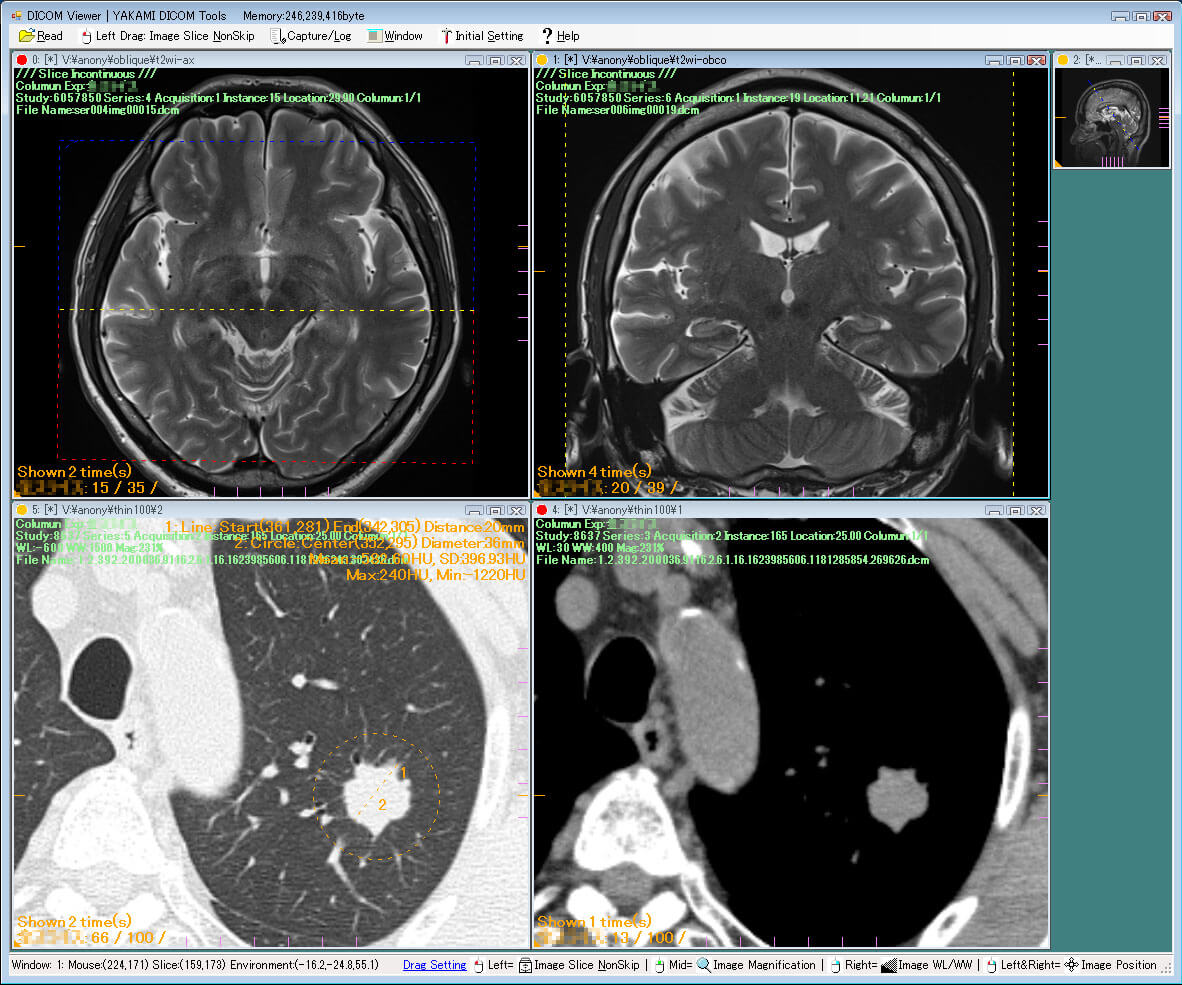

| 25. | Yakami DICOM | Windows | Not available | Y | Y | Y | N.A. | 1 GB | Intel processor/ 2 GB RAM | Free for non-commercial use |